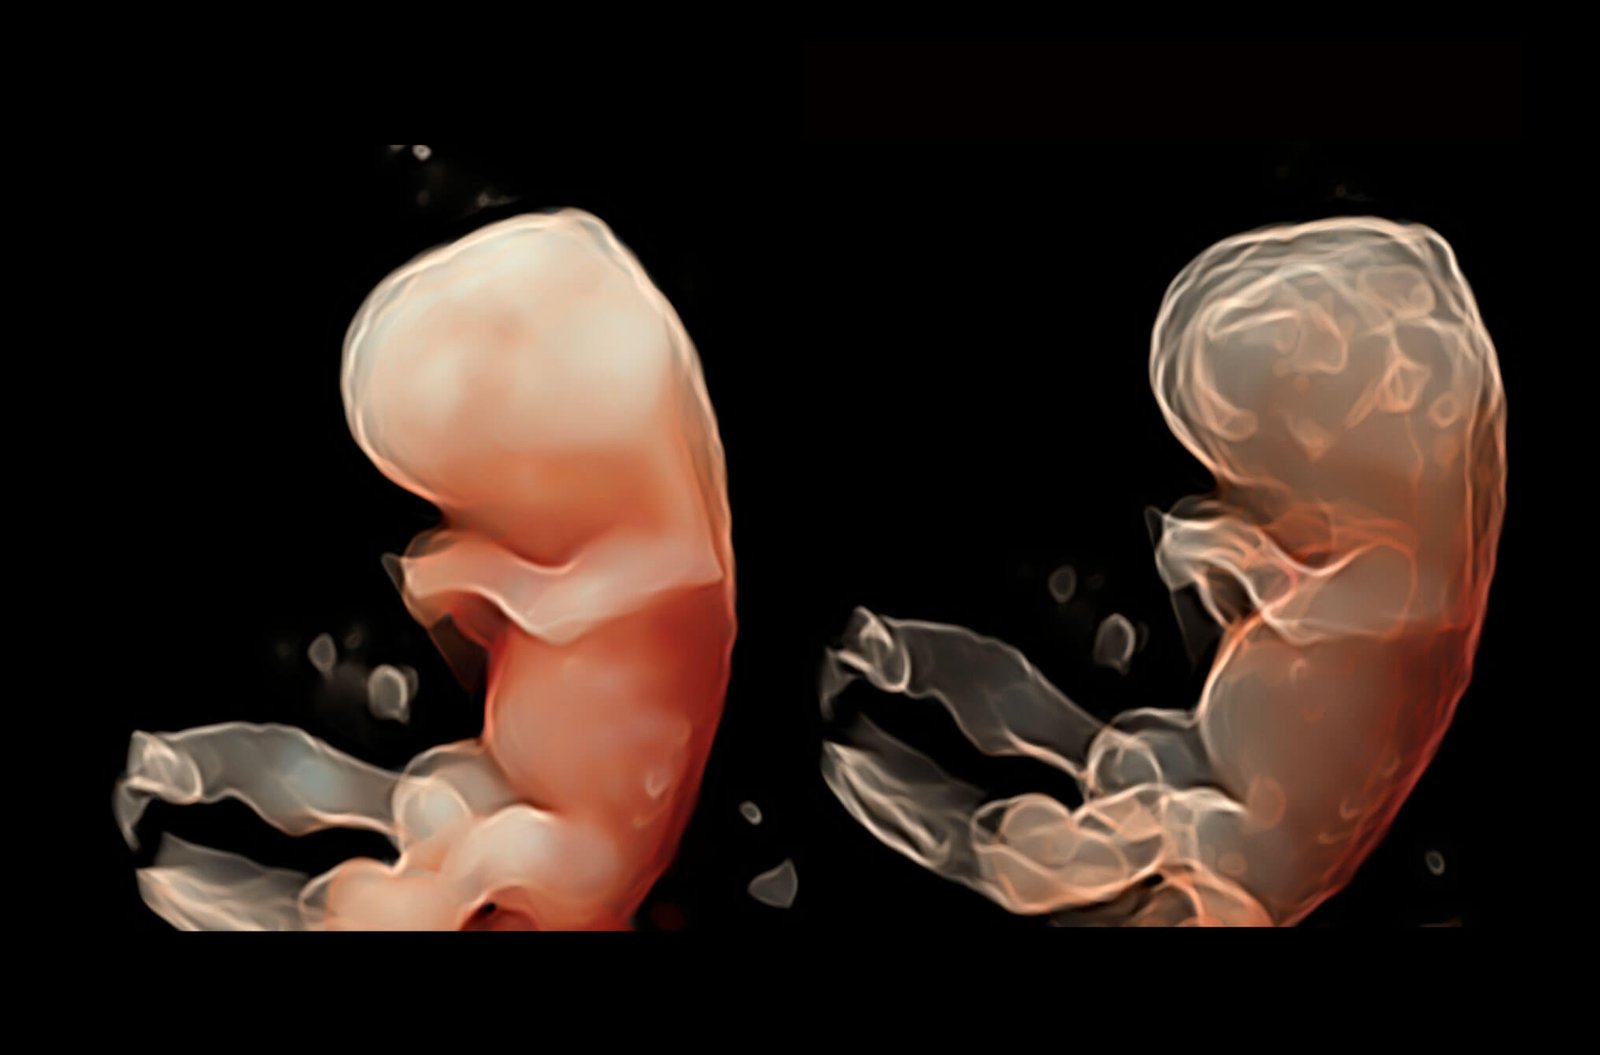

Ultra-light Crafted Volume VC2-9

Reduced weight, ultra-wide bandwidth, exquisite resolution and penetration at high volume rate, VC2-9 is a one-probe-solution throughout nearly the entire pregnancy.